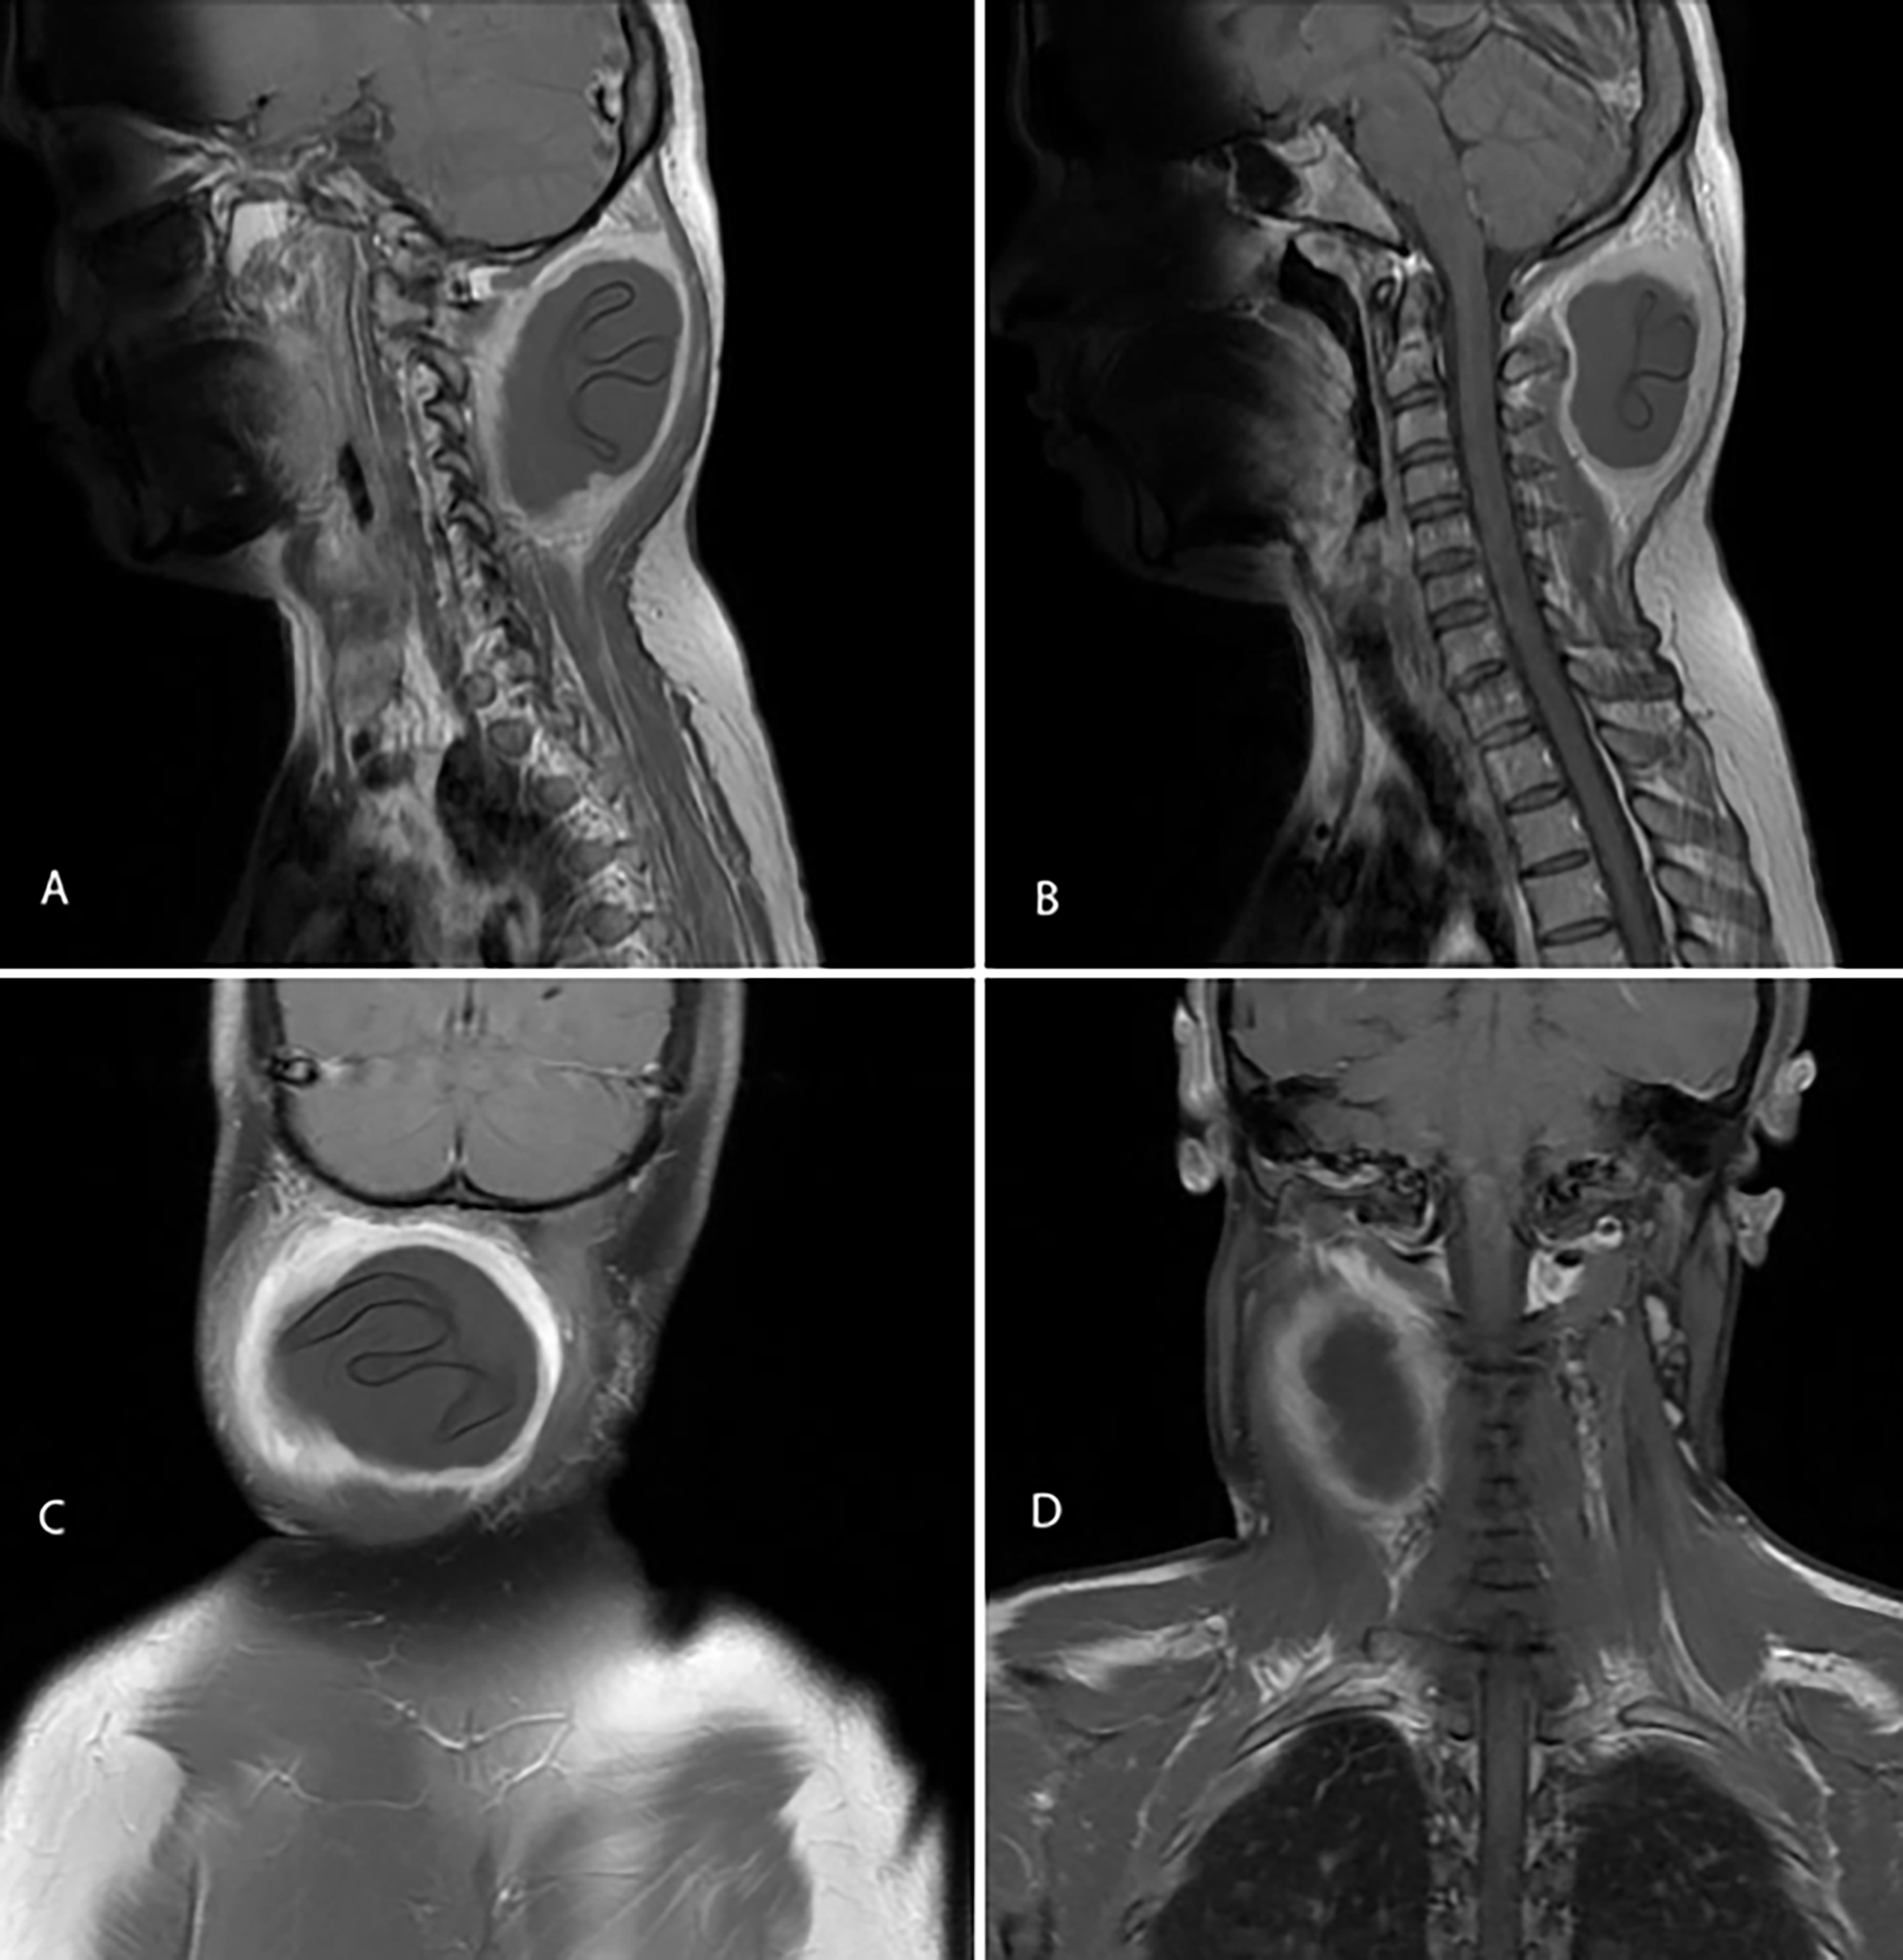

On examination, there was a single, globular swelling in the posterior triangle of the neck, measuring approximately 5 × 5 cm, extending from the occiput to the nape. The swelling was soft to cystic in consistency, non-mobile, and non-tender. It was not adherent to the overlying skin but was fixed to the underlying musculature. No punctum or sinus was present. There was no bruit on auscultation, and regional lymph nodes were not enlarged. Ultrasonography revealed a well-defined hypoechoic cystic lesion measuring 5.3 × 4.6 × 6.4 cm on the right lateral aspect of the neck, initially suggestive of a cold abscess. FNAC demonstrated scattered keratin flakes and mildly acellular keratinous material. Complete blood count (CBC) was within normal limits, whereas liver enzymes were mildly elevated. There was no laboratory evidence of systemic infection. CT of the neck demonstrated a hypodense lesion in the right neck region measuring approximately 5.7 × 6.0 cm, with peripheral post-contrast enhancement. Within the lesion, a second similar-density structure representing floating membranes was noted, measuring 7 cm craniocaudally. The mass caused focal skin bulging to the midline and displaced the adjacent erector spinae and paravertebral muscles medially (Figure 1).

Figure 1: Coronal (A) and axial (B) contrast-enhanced CT scans of the neck demonstrating a hypodense lesion in the right paravertebral region with peripheral post-contrast enhancement. An internal similar-density component, consistent with floating membranes, is seen measuring approximately 7 cm craniocaudally, producing focal skin bulging toward the midline and displacing the adjacent erector spinae and paravertebral muscles medially.